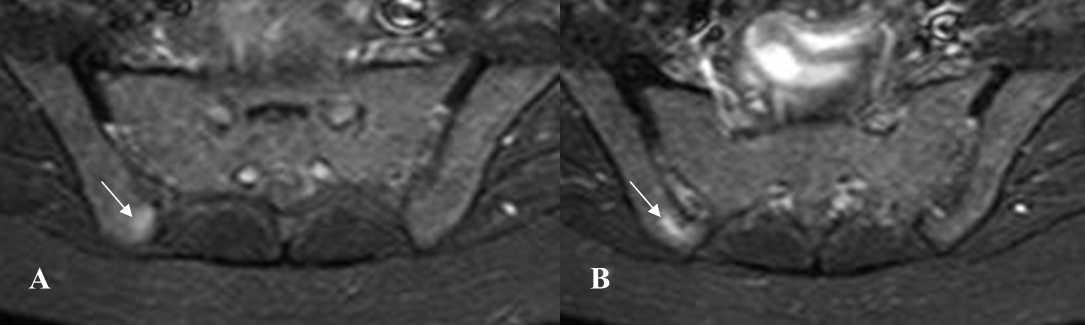

Fig 58 A. Espondilitis anquilosante.

A y B: RM axial en STIR. Edema trabecular en los alerones del sacro a nivel bilateral y el iliaco izquierdo. (Flechas delgadas). Con tratamiento y en un control realizado 2 años después, han desaparecido los cambios inflamatorios agudos. En ambas imágenes hay lesiones de evolución crónica, sobre los iliacos. (Flechas gruesas).